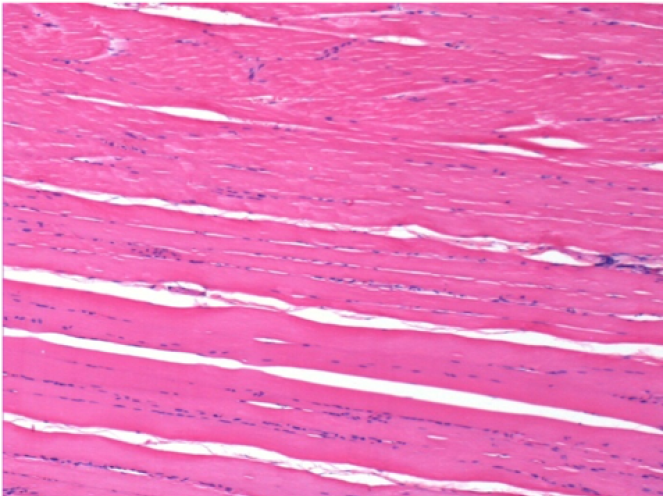

L:Pretibial-No treatment

L :Control 50xD210

L:200x-Control-SC